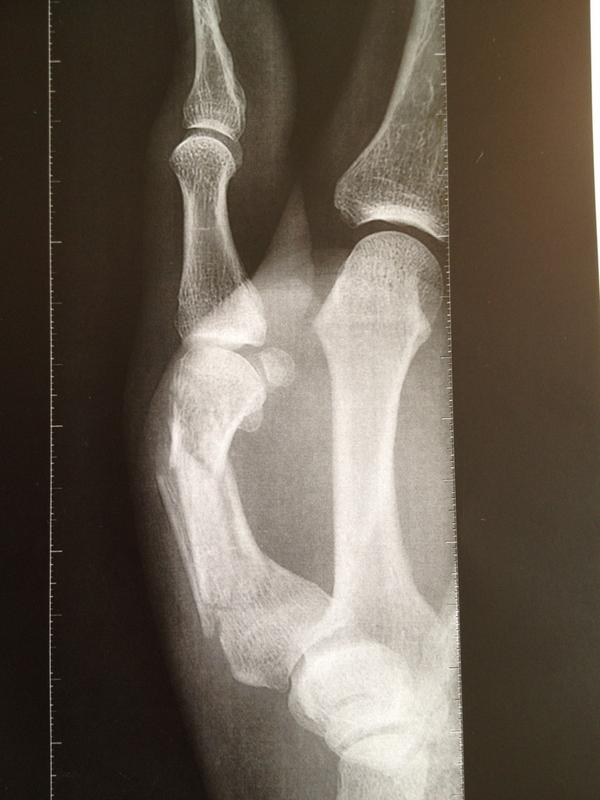

Jerome Fernadez: 2 meses fuera de las canchas Jerome Fernadez, primera línea del Toulouse de la Liga Nacional Francesa, estará casi dos meses fuera de las canchas por fractura en el primer metacarpiano.La fotografía fue difundida por el mismo Jerome en su Twitter:@JrmeFernandez Mundo Handball lunes, octubre 08, 2012 Share to: Twitter Facebook URL Print Email Etiquetas: destacado Jugadores Protagonistas